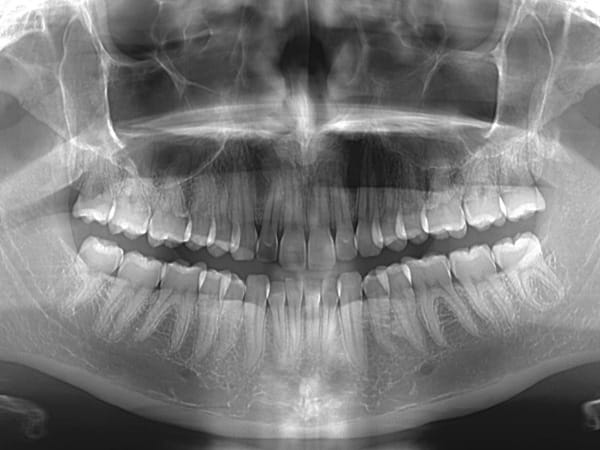

Detailed Imaging Of Your Teeth, jaw, And Surrounding Structures.

Dental scans provide:

• Accurate diagnoses of cavities, infections, or abnormalities not visible during a regular examination.

• Bone density assessments for implants or orthodontic planning.

• Detection of impacted teeth or cysts.

• Precise treatment planning for advanced procedures.